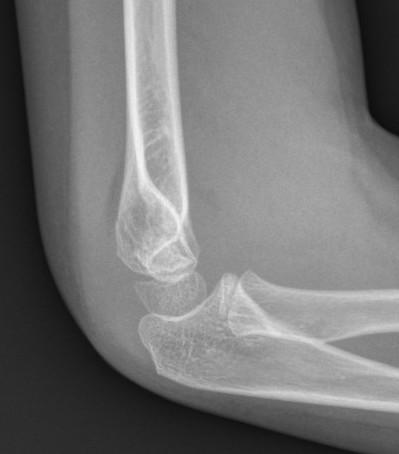

Gartland III - Displaced, nil cortical contact

- completely displaced

- posteromedial or posterolateral

Type IIIA Posteromedial

Commonest

- distal fragment goes posteromedial

- cause cubitus varus

- injures radial nerve which is tethered over lateral spike on proximal fragment

- manage by pronation which tightens medial periosteal hinge

Type IIIB Posterolateral

Distal fragment goes posterolateral

- causes cubitus valgus

- tend to ER

- injuries median nerve & brachial artery

- these get tethered over medial spike on proximal fragment

- manage by supination which tightens lateral periosteal hinge

The position of stability is achieved with the thumb pointed towards the side of the periosteal disruption